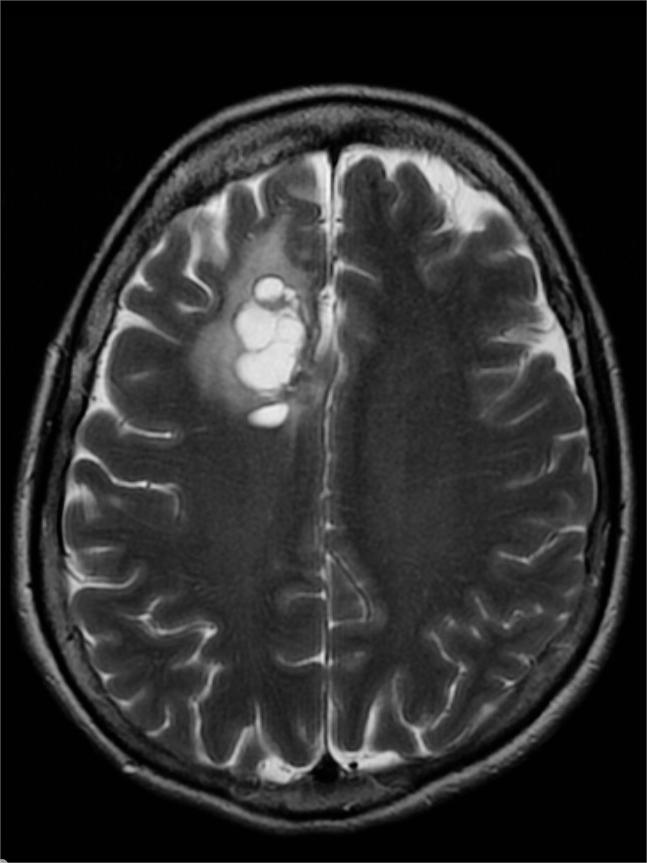

小脑发育不良性神经节细胞瘤!

小脑皮质弥漫性神经节细胞瘤